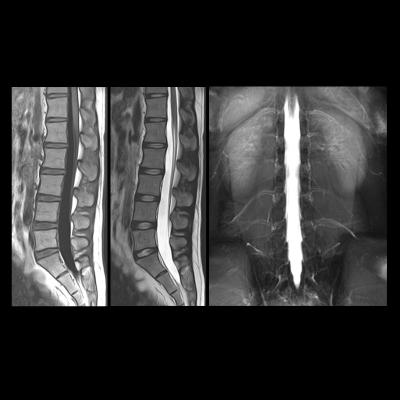

That barrier was overcome for the first time in this study by taking advantage of the fact that the 3.0T MRI scanner had a field of view long enough to image the brain and the cervical spinal cord, which relays signals to and from the hand muscles. Using this technique on subjects performing a complex finger tapping task, the authors showed that learning-related changes in blood flow in the spinal cord were independent of changes in blood flow in the brain regions involved in the task.